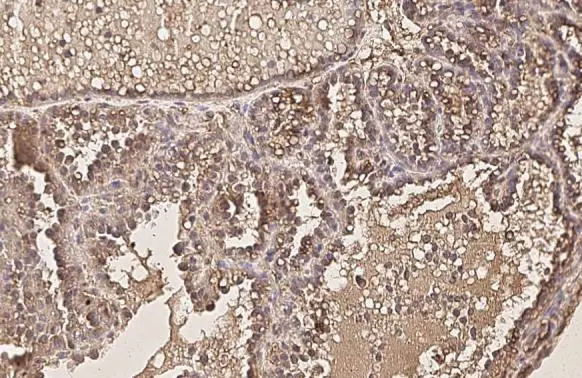

Anti-AKT1 antibody [HL1142] used in IHC (Paraffin sections) (IHC-P). GTX636413

GTX636413 IHC-P Image

AKT1 antibody [HL1142] detects AKT1 protein at cell membrane and cytoplasm by immunohistochemical analysis.

Sample: Paraffin-embedded cat mammary gland.

AKT1 stained by AKT1 antibody [HL1142] (GTX636413) diluted at 1:100.

Antigen Retrieval: Citrate buffer, pH 6.0, 15 min